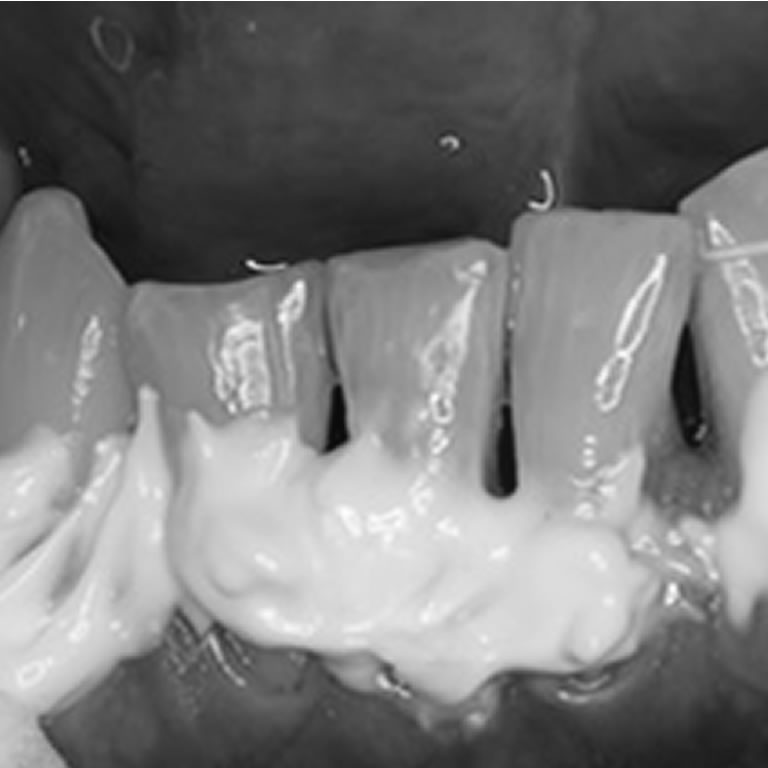

Operatoria Dental y Endodoncia

Dr. Osvaldo Zmener

El artículo aborda la relación entre operatoria dental y salud pulpar, destacando la importancia del diagnóstico adecuado, la protección del complejo dentinopulpar y las técnicas restauradoras que minimizan lesiones, favorecen la preservación pulpar y mejoran el pronóstico clínico.